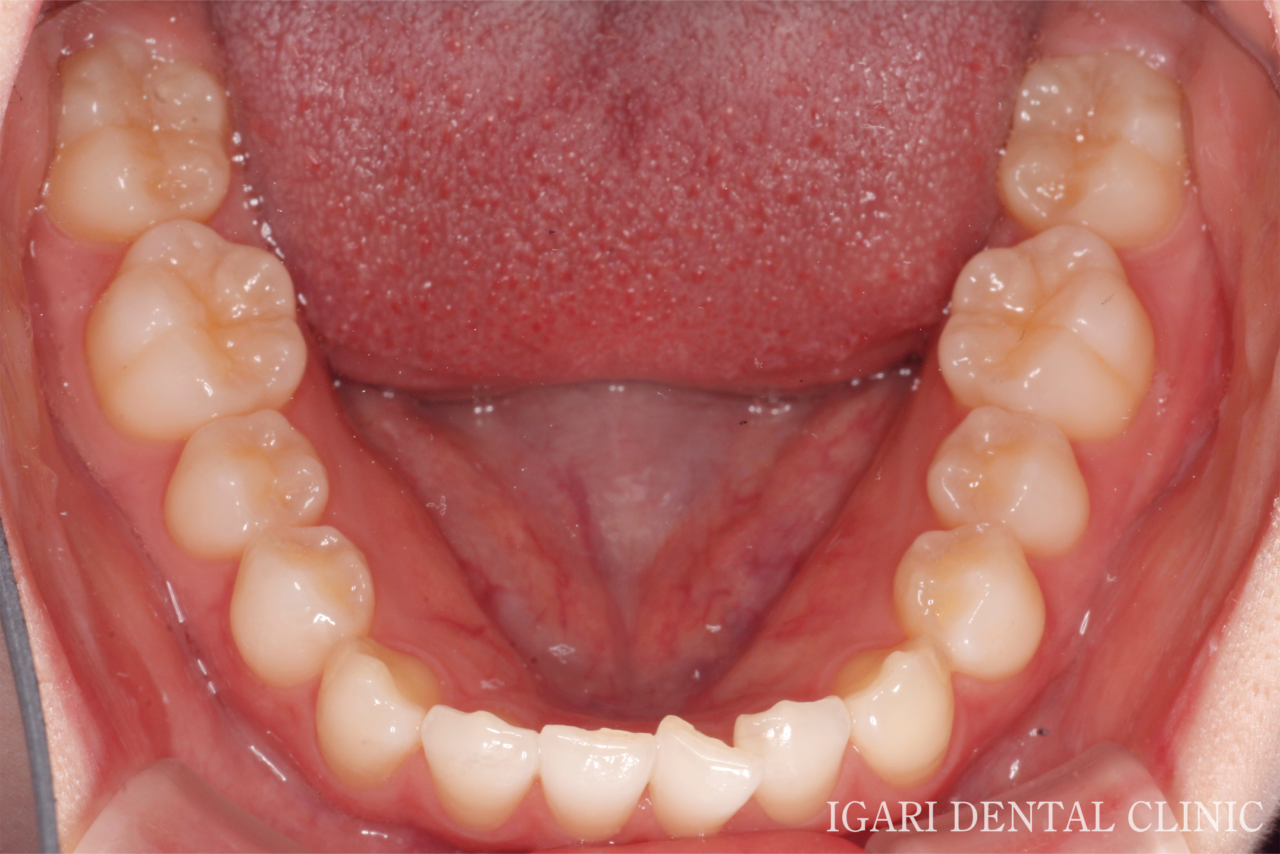

治療前下顎

真ん中右上の歯がねじれながら傾いて生えており(翼状捻転)、上下の前歯に重なり(叢生)がみられました。

また、左側の犬歯が低い位置にあり、いわゆる八重歯の状態でした。 -